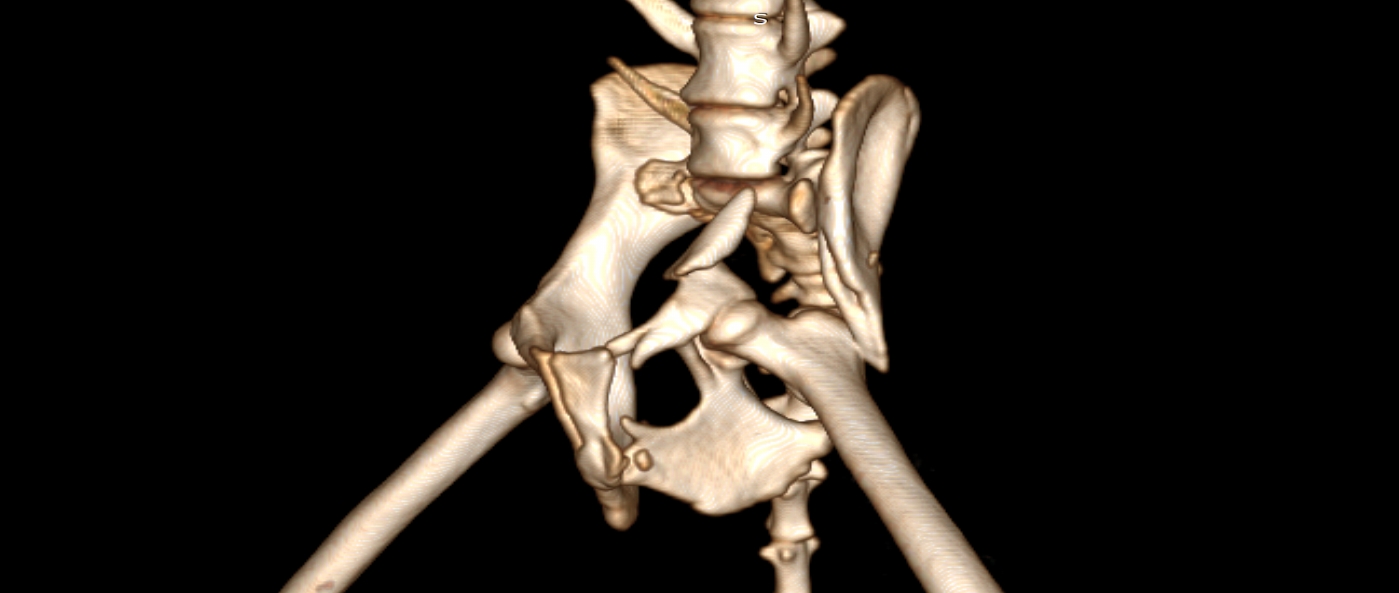

狗狗 車禍 骨盆骨折

狗狗的骨盆骨折相對於常見的四肢骨折 不容易單純靠xray 診斷及擬定手術計畫藉由電腦斷層影像的支援 能提高手術成功的機率

14kg 11歲的莓莓 術後10個月追蹤 行動自如一切正常喔

骨盆骨折 評估手術計畫